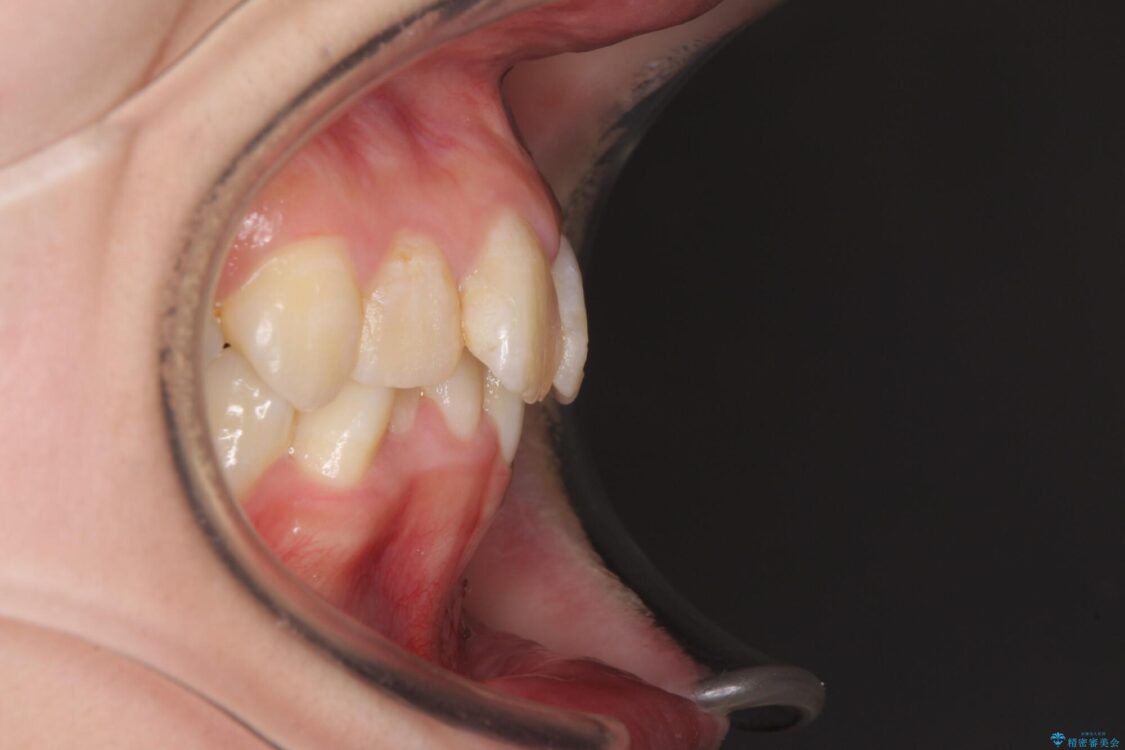

内側に倒れ込んだ歯や下の前歯が隠れてしまうほどの咬み合わせを改善したいとのことで来院された患者様です。

下顎の叢生を解消するために抜歯が必要であり、奥歯の咬み合わせや口元の印象から、上顎も同様に抜歯と判断し、上下左右の第1小臼歯4本抜歯してワイヤー装置にて矯正治療を行うこととしました。

咬み合わせが深く、そのままでは上顎の抜歯スペースが閉じきらない可能性があったため、治療初期から深い咬み合わせを改善させるように試みました。

実際にはなかなか改善されず、当初予定よりも治療期間がやや長期化してしまいました。

治療途中

• デコボコと深い咬み合わせ ワイヤー装置での抜歯矯正 治療途中画像